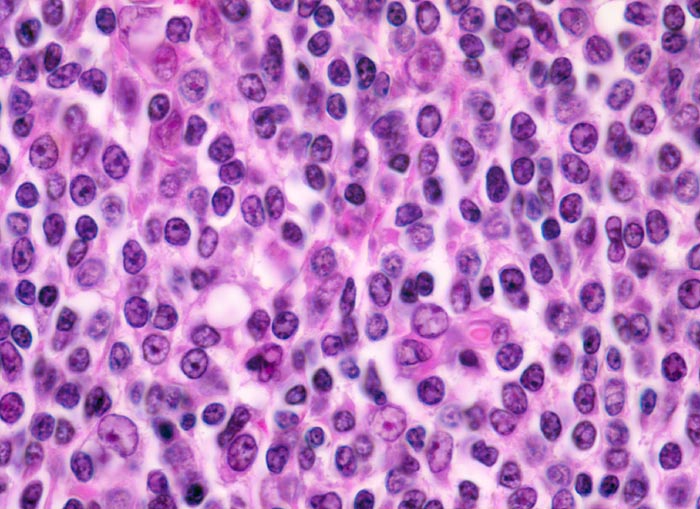

extranodales Marginalzonenlymphom vom MALT-Typ

Das neoplastische Infiltrat besteht aus kleinen zentrozytoiden Zellen mit leicht entrundeten Kernen und wenig Zytoplasma. Eingestreut einzelne immunoblastäre Zellen.

Histologie

400